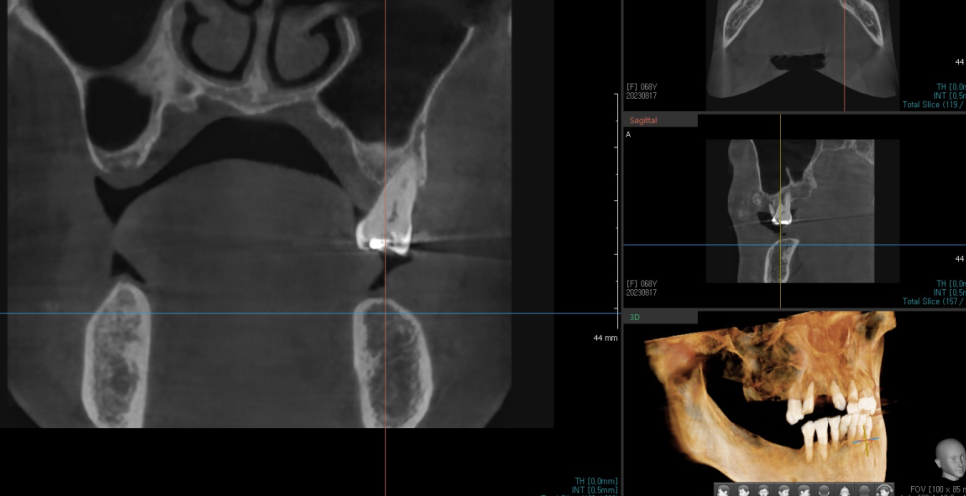

230817

ct도 찍어 남아있는 잇몸 뼈를 분석

예후를 예측하여 몇개를 뽑고

임플란트가 필요할지

전체적인 치아 치료 진단을 진행합니다.